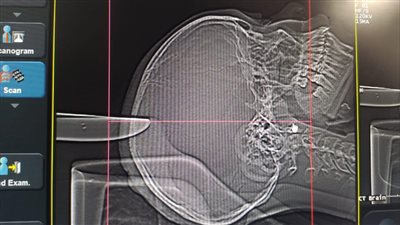

بعد طعنها بسكين في الرأس.. تفاصيل نجاح جراحة دقيقة لطفلة بالأقصر